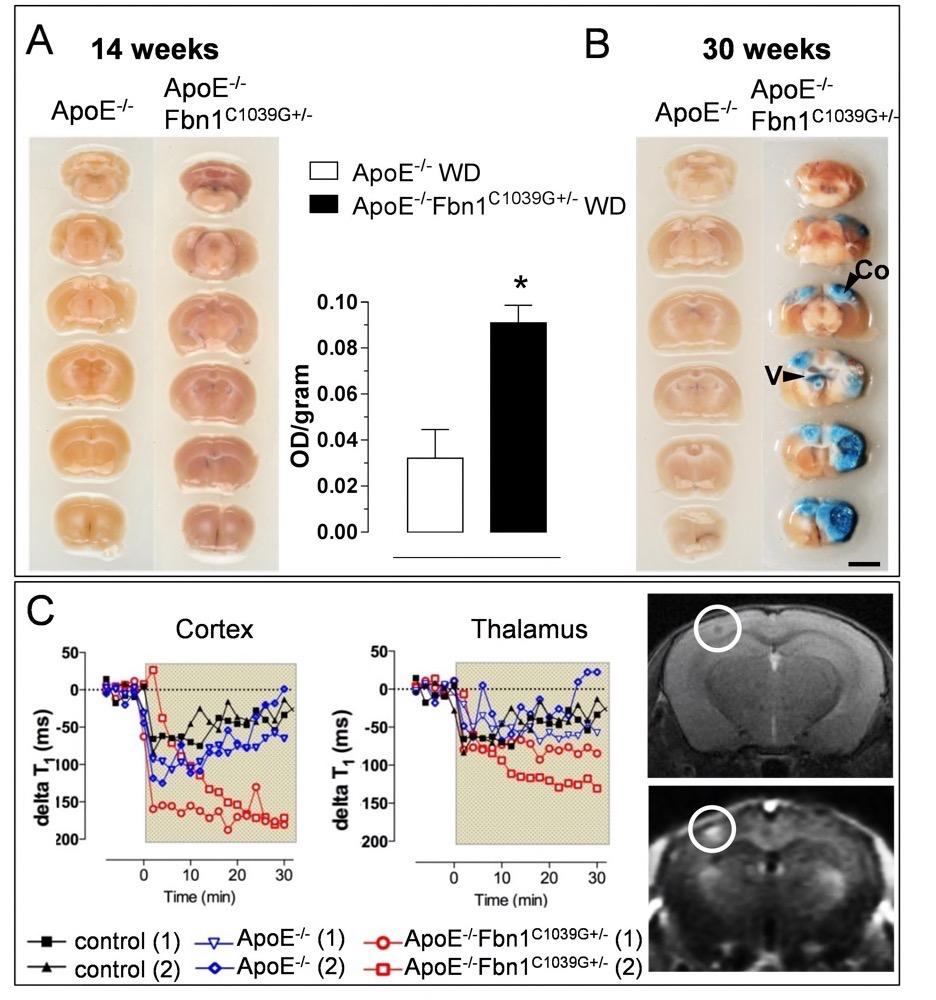

Chapter 4 Figure 2Increased BBB/BCSFB permeability in ApoE-/-Fbn1C1039G+/- mice. (A) After 14 weeks on WD, a significant Evans blue leakage is observed in brains of ApoE-/-Fbn1C1039G+/- compared to ApoE-/- mice (spectrophotometric quantification in the right hand panel). (B) After 30 weeks on WD, ApoE-/-Fbn1C1039G+/- mice show impressive lesions in large areas of (neo)cortex (Co) and brain ventricles (V), which are associated with extensive Evans blue leakage, pointing toward a breakdown of the BBB/BCSFB. Different gradients of Evans blue are observed in the lesions (n=4 per group, P=0.018, unpaired Student’s t-test). Spectrophotometric quantification of Evans blue at 30 weeks could not be performed due to the large presence of lesions (lipids), interfering with the measurement. (C) Gadolinium (Gd)- enhanced MRI at 21 weeks on WD showed an increased drop in delta T1 values in ApoE-/-Fbn1C1039G+/- mice (red) compared to ApoE-/- (blue) and WT control mice (black). (1) and (2) represent two different mice, representative of each group. Gd leakage was more pronounced in the neocortex of ApoE-/-Fbn1C1039G+/- mice and peaked in the presence of a lesion (white circle).Right hand panel: upper T2 and lower T1-weighted image.